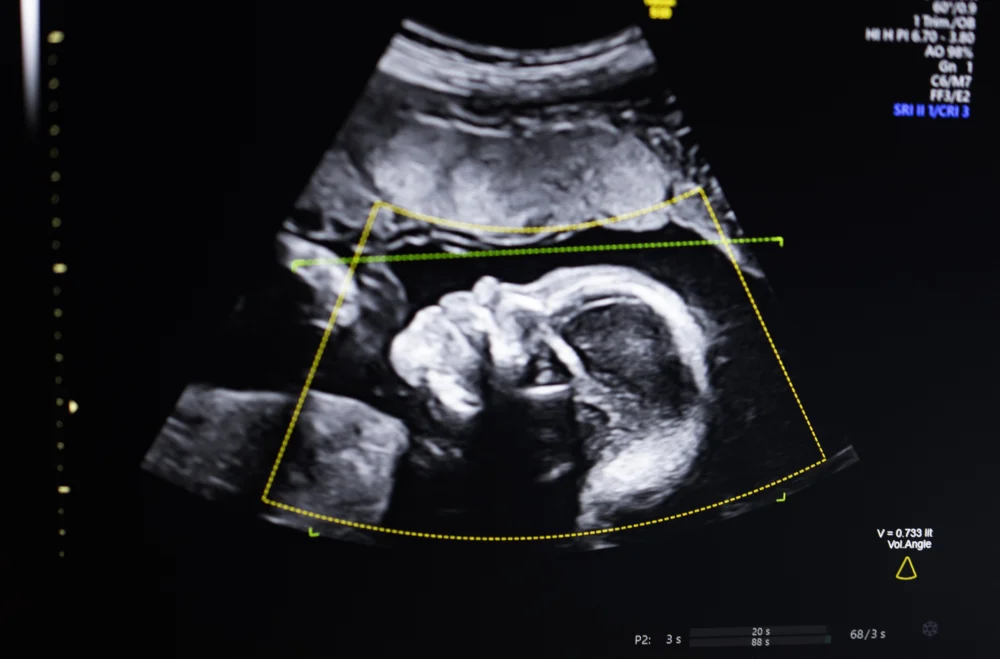

The prenatal ultrasound examination is universally acknowledged as the cornerstone of contemporary pregnancy surveillance. It provides essential non-invasive visual data used to monitor fetal growth, assess placental health, and, most critically, screen for structural abnormalities. However, the efficacy of this diagnostic tool is inherently limited by several factors, primarily the dependence on operator skill and the often-low inherent quality of the images produced by standard equipment. As Bustami has noted, this variability in image quality often translates directly into the risk of misdiagnosis or delayed detection of critical fetal anomalies, which can have tragic consequences.

BioticsAI’s platform is engineered to directly address this inconsistency. By utilizing computer vision AI, the software acts as an intelligent co-pilot, meticulously reviewing the scan in real-time. It verifies that all necessary anatomical structures have been captured—a crucial element of achieving a "complete" Level II ultrasound—and assesses the technical quality of the captured views. This level of algorithmic rigor ensures that regardless of whether the scan is performed in a specialized tertiary care center or a remote, resource-constrained clinic, a standardized benchmark of image acquisition and diagnostic completeness is met.

- Integration with 3D/4D Imaging: Extending the quality and completeness checks to three-dimensional ultrasound data, which provides deeper anatomical detail but requires more complex rendering and interpretation.